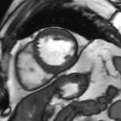

心脏成像 --- 压缩感知电影

自由呼吸,无需屏气

捕获全心动周期数据

临床价值

成像速度和图像质量同时提升

定量数据更精准

心脏MR适用人群更广

实例展示

压缩感知

传统实时

传统分段

心脏电影---房颤病人图像质量对比